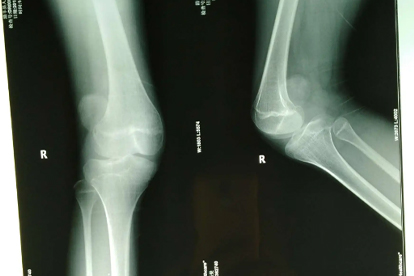

髌骨脱位可能由先天发育异常、外伤性损伤、肌力失衡、韧带松弛及骨骼结构异常等因素引起。髌骨脱位主要表现为膝关节疼痛、肿胀、活动受限等症状,需结合影像学检查确诊。

高位髌骨或胫骨结节外偏等畸形会改变髌骨运动轨迹。影像学测量Insall-Salvati指数超过1.2提示高位髌骨。矫正手术包括胫骨结节内移术或髌腱止点下移术,术后需严格避免早期负重。